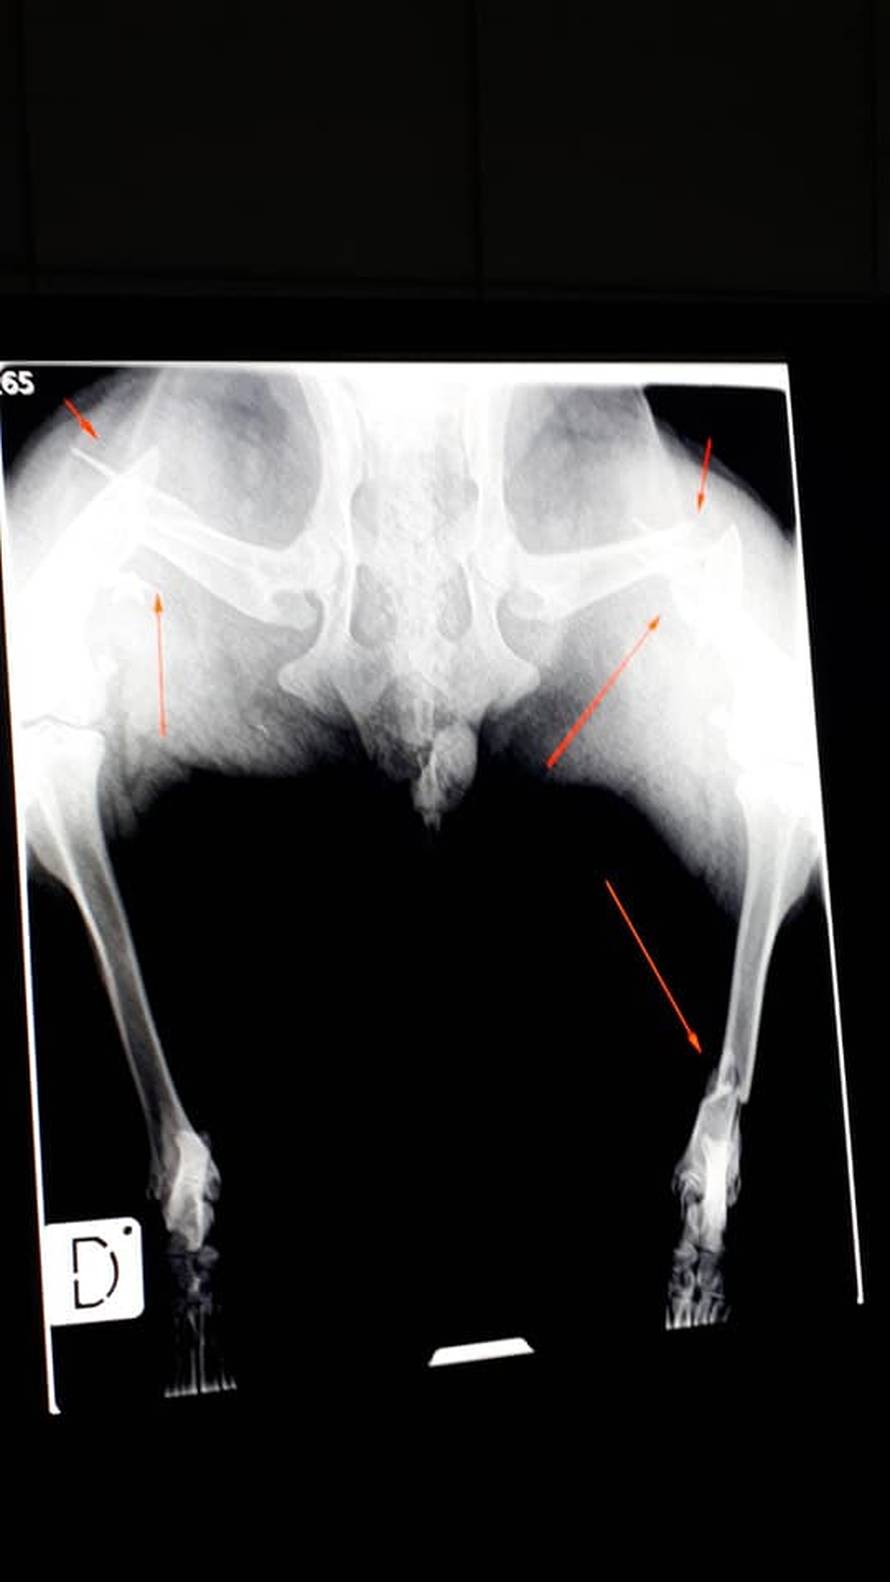

Vozač traktora iz mjesta Rašljeva iz BiH namjerno je nekoliko puta pregazio ženku haskija. Potom ju je odnio i zaključao na svom imanju. Pas je spašen i oporavlja se